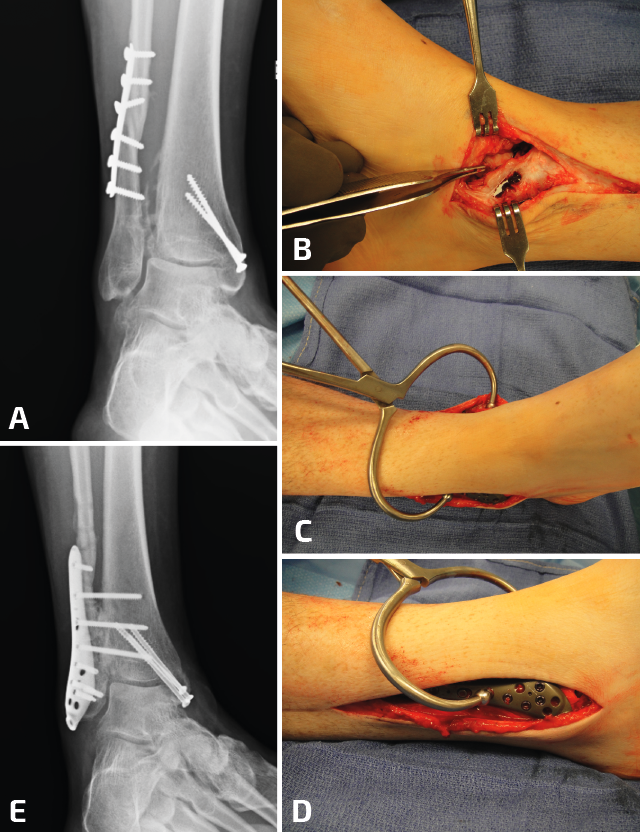

Una vez más, se desbrida el tejido fibrótico de la cara interna del peroné, pero se deja intacto el ligamento talofibular anterior y el ligamento calcáneo fibular. Para este tipo de osteotomías transversas es importante comprender que, en el proceso de elongación del peroné, al insertar el separador laminar o utilizar el distractor de agujas, se empujará simultáneamente el peroné hacia proximal(10). Por lo tanto, resulta útil insertar 1 o 2 agujas de 1,6 mm en el peroné en la zona proximal a la osteotomía pasando por la tibia para evitar el movimiento del peroné hacia proximal y que solamente se produzca la elongación distal (Figura 4). Una reconstrucción exitosa requiere el posicionamiento anatómico del maléolo externo en la escotadura peronea de la tibia que solo puede detectarse con visualización directa.

La distracción estable es importante durante el procedimiento de elongación del peroné, dado que permite una colocación más sencilla del material de osteosíntesis. Se han descrito varios métodos para poder fijar el astrágalo a la cara interna de la tibia: se pueden utilizar clavos Steinmann desde el peroné distal hasta el astrágalo, o bien se puede insertar una aguja para fijar al astrágalo contra la cara interna de la tibia, cerrando así el espacio de la gotera medial. Otra alternativa sería la utilización de una pinza de reducción de puntas que se coloca en el extremo distal del maléolo externo y el extremo distal del maléolo interno para restablecer el ángulo intermaleolar. Tras una correcta elongación y rotación, se restablece el espacio claro medial, el paralelismo entre las superficies articulares de la tibia y el astrágalo en la mortaja, y una correcta relación entre ambos maléolos (Figura 5).

Figura 5. En este caso, se observa ensanchamiento de la sindesmosis más consolidaciones viciosas del peroné y el maléolo medial (A). Se debe comenzar por la gotera medial para limpiar todo el tejido cicatrizal remanente. La incisión fue más larga de lo habitual, ya que se planificó una osteotomía del maléolo medial. Tras la reducción y la elongación del peroné, se coloca una pinza de reducción en el eje axial entre la tibia y el peroné (C, D). Al continuar con inestabilidad posterior a la colocación de 2 tornillos (E), se decidió realizar una artrodesis de la sindesmosis